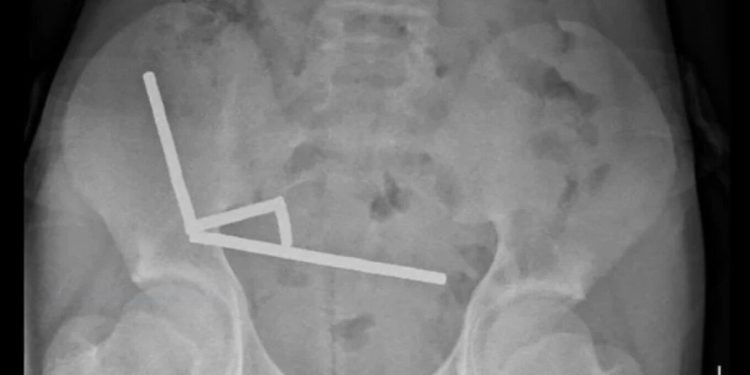

Rrezet X zbuluan se magnetet kishin formuar katër grumbuj të drejta brenda zorrëve. Ato ishin vendosur në pjesë të ndryshme të zorrëve dhe ngjitur së bashku tërësisht nga forcat magnetike. Si pasojë e këtij grumbullimi, kishte ndodhur nekrozë në katër zona të zorrës dhe cekumit, një pjesë e zorrës së trashë. Kirurgët ndërhynë për të hequr indin e vdekur dhe për të rimarrë magnetët.